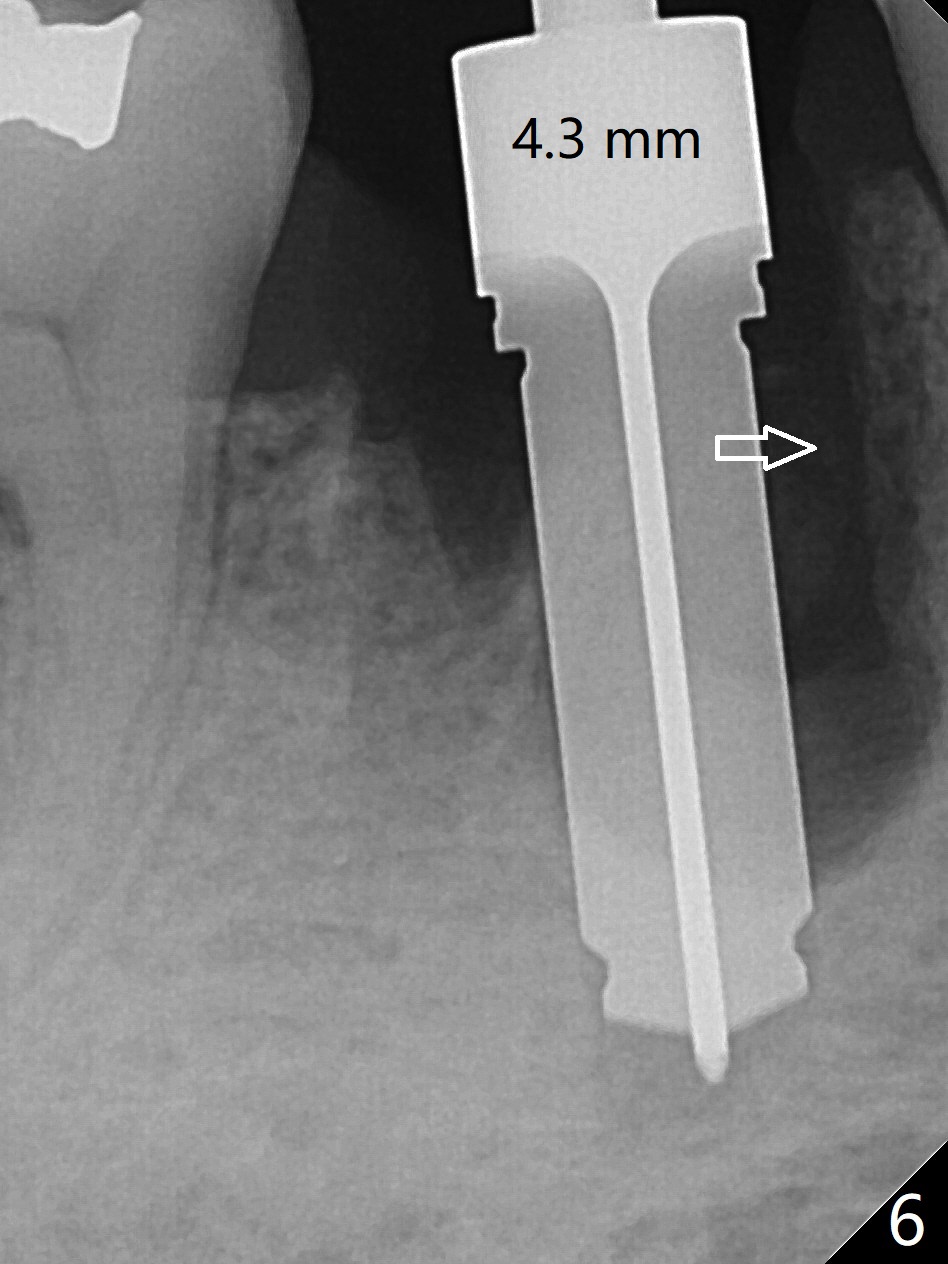

Preop oral Amoxicillin seems to be associated with reduction in the buccal and lingual (Fig.3 arrow) fistulae at #30, but there is mesiobuccal swelling (Fig.1 *) with 7 mm pocket (Fig.2). Osteotomy is initiated in the middle of the septum (Fig.3-5 S). As the osteotomy increases, it shifts mesially (Fig.6 arrow). Guided surgery is able to reduce shifting. A 5x13 mm implant is not seated completely (Fig.7) apparently due to osteotomy shifting. After removal of the bone from the osteotomy distally, the implant remains unseated with lower torque value (Fig.8). Following reuse of the 4.3 mm drill deeper by 1-2 mm, the implant is seated to a satisfactory depth (Fig.9 with increase in torque to 50 Ncm) with placement of Vera Graft (*) and a 7.5x4(3) mm abutment. After a second round of allograft placement (Fig.10 *), the implant is found to be 4 mm from the IAC. At the later stage of osteotomy, the coronal end of the septum is destroyed with loss of osteotomy depth landmark. It is apparent that the soft tissue landmark may be more reliable. The implant threads appear to be covered by the bone graft 3.5 months postop (Fig.11). The abutment is changed to 6.5x5(3) mm one before impression with minor margin prep. The bone density seems to increase 5 months postop, i.e., immediately post cementation (Fig.12) and 10 months postop (5 months post cementation (after retightening abutment), Fig.13 (*)). Periimplantitis develops mesiobuccally, consistent with bone loss 1 year 7 months post cementation (Fig.14 *); the implant seems to have been buccally placed. Bone graft is necessary with PRF or GEM21S if the vein is small and 6-month membrane with a hole around a 7.5x4(4) cemented abutment for easy wound closure. Take 5x5 CM CBCT to determine which wall has defect, buccal or lingual. Check mesial contact. If so, remove the crown, reseat the abutment (possible incomplete seating) and re-impress after bone graft.